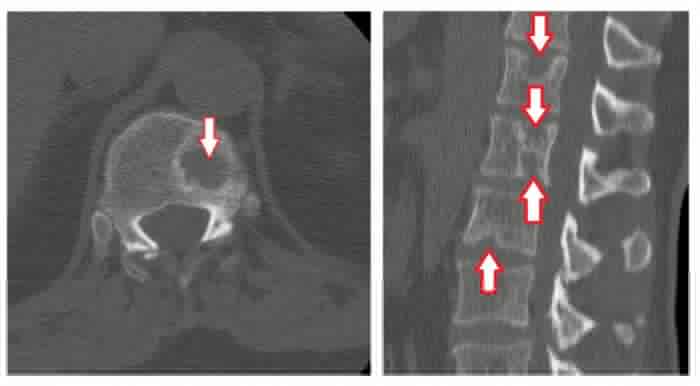

Грыжи межпозвонковых дисков при КТ позвоночникаклассифицируются в зависимости от их локализации. Так, выделяют задние, латеральные и передние грыжи дисков — в зависимости от того, в какую сторону выпадает межпозвонковый диск. Задние грыжи в свою очередь могут быть центральными (диск выбухает кзади по средней линии), медиаолатеральными (диск выбухает в латеральный карман справа либо слева), фораминальными (диск выбухает в межпозвонковый канал). Грыжа диска может быть также внутрикостной (по типу т. н. грыжи Шморля) — при этом происходит пролабированиепульпозного ядра в тело позвонка с проламыванием его замыкательной пластинки.Грыжа Шморля при компьютерной томографии позвоночника выглядит как дефект тела позвонка, отграниченный плотным склерозированным «ободком». Редко встречается также вариант интрадурального пролапса (грыжи), когда секвестр распространяется под твердую оболочку спинного мозга.

Самая частая локализация межпозвонковых протрузий и грыж — поясничный отдел позвоночника. Так, задняя продольная связка натянута в поясничном отделе гораздо слабее по сравнению с грудным (вследствие наличия поясничного лордоза), а давление на межпозвонковые диски (особенно в нижних — L4-L5, L5-S1 — сегментах) больше, чем в грудном и шейном отделах.

Пример парамедианной грыжи межпозвонкового диска в пояснично-крестцовом сегменте позвоночника при компьютерной томографии (грыжа диска отмечена стрелкой). В диске визуализируются также включения газа («вакуум-фемонен»), отмечены красной звездочкой «*».